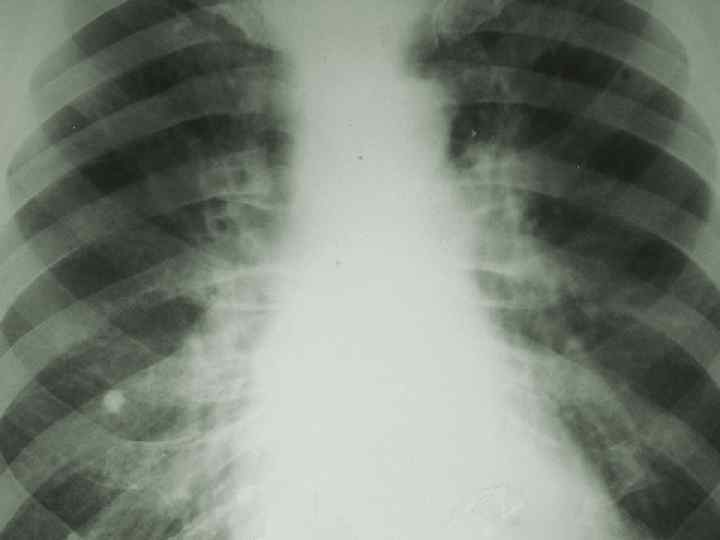

Туберкулез внутригрудных лимфоузлов n Клинико - рентгенологические формы: малая, n инфильтративная, n туморозная. n

Туберкулез внутригрудных лимфоузлов (инфильтративная форма) n n Диагностика Вираж туберкулиновых проб; Рентгенографически и томографически: расширение тени корня легкого, границы нечеткие.

Туберкулез внутригрудных лимфоузлов (туморозная форма) n n Диагностика Вираж туберкулиновых проб; Рентгенографически и томографически: значительное расширение тени корня легкого, границы четкие.

Туберкулез внутригрудных лимфатических узлов